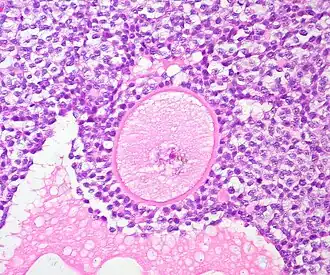

Artificial ovary

Graafian follicle of the human ovary